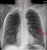

Large pneumothorax - early tension

- A large pneumothorax is usually easy to recognise, but always check for signs of tension.

- Rising pressure within a hemithorax reduces venous flow to the heart, potentially leading to rapid death.

Signs of tension

- Right heart border (white arrows) and left heart border (black arrows) shifted to the left

- Right hemidiaphragm slightly depressed - should be higher than the left

- Minor shift of the trachea - unlikely to be clinically detectable

- Don't waste time discussing the exact definition of a tension pneumothorax - this patient needs attention - NOW! Start with ABC and get help